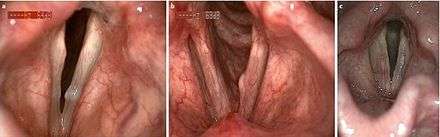

Mucous retention cysts are most commonly seen in individuals that endure high vocal stress in their daily lives, while epidermoid cysts are usually congenital or second to vocal trauma (see lead section for more information on different types of cysts).[5] The two types of vocal fold cysts can be differentiated from other vocal fold growths in several ways. Both types show decreased amplitude of vibrations and reduced or absent mucosal wave.[5] Mucous retention cysts show a translucent mass of mucous usually below the free margin of the glottis, while epidermoid cysts are yellow masses under the first epithelial layer of the vocal folds.[4] Epidermoid cysts generally appear in the superior and medial regions of the midmusculomembranous region of the folds, as opposed to mucous cysts appearing in the inferior region.[7] Vocal fold cysts are differentiated from other vocal fold masses in that they are unilateral and subepithelial.[7]

Four components to a full diagnosis are: medical and voice history, head and neck exam, then perceptual assessment of voice and imaging of vocal folds.[4] The primary perceptual sign of vocal fold cysts is hoarseness of the voice.[7] However, diagnosis is difficult; in most cases, when a diagnosis cannot first be reached via behavioural assessment and intervention, the patient undergoes an imaging procedure.[2] Imaging is most commonly done with laryngeal videostroboscopy.[4] This procedure provides information about vocal fold vibrations during speech, vocal intensity and vocal frequency.[4] Imaging shows the reduced movement of the vocal folds (mucosal wave) when a vocal fold cyst is present.[4]